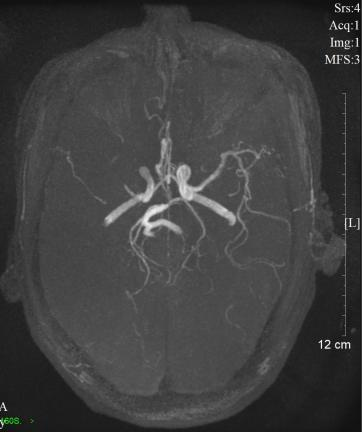

注:图 1 图 2 均为头颅动脉血管磁共振检查结果图片,图 1 为脑梗患者的动脉血管显像,红色箭头处表示该处有血栓堵塞,造成远端血管没有血流通过,以至于远端血管没有显影;图 2 为正常颅脑动脉血管,双侧血管对称显示清楚。